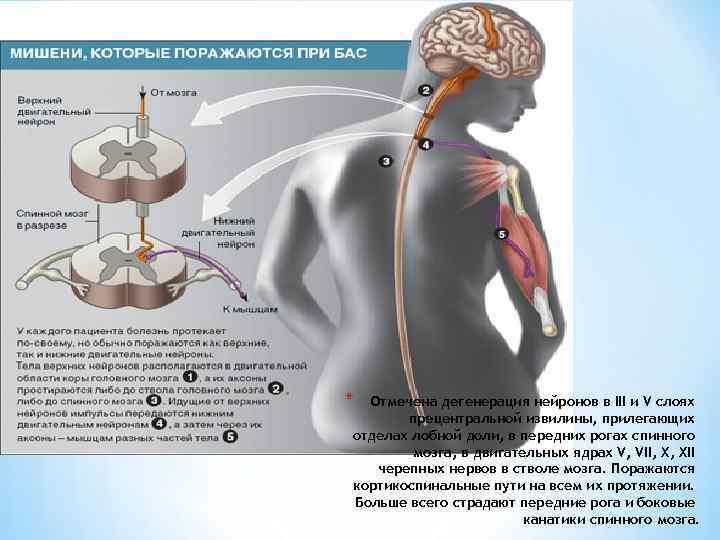

* Отмечена дегенерация нейронов в III и V слоях прецентральной извилины, прилегающих отделах лобной доли, в передних рогах спинного мозга, в двигательных ядрах V, VII, X, XII черепных нервов в стволе мозга. Поражаются кортикоспинальные пути на всем их протяжении. Больше всего страдают передние рога и боковые канатики спинного мозга.

* Отмечена дегенерация нейронов в III и V слоях прецентральной извилины, прилегающих отделах лобной доли, в передних рогах спинного мозга, в двигательных ядрах V, VII, X, XII черепных нервов в стволе мозга. Поражаются кортикоспинальные пути на всем их протяжении. Больше всего страдают передние рога и боковые канатики спинного мозга.